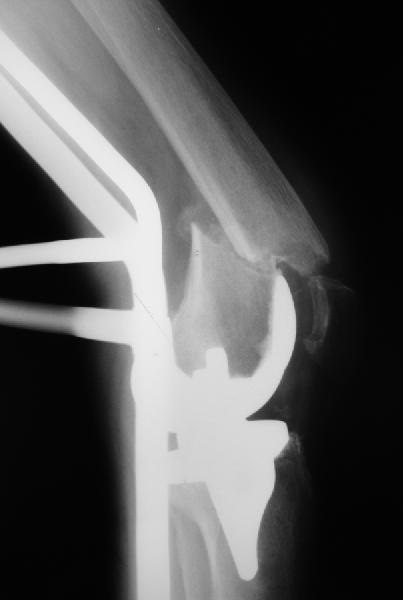

Re: перипротезный перелом

То, что планируется - наиболее распространенный подход. Еще менее инвазивный вариант - закрытый антеградный интрамедуллярный остесинтез. Мы используем гвозди, которые выпускаются предприятием ЦИТО, т.е. недорогие. Там в дистальное отверстие можно ввести 3 винта (2 снаружи и один навстречу), еще и угловая стабильность получается.

Александр Николаевич, сколько у вас таких клиентов? Каковы исходы? Только ли ЦИТОвские стержни использовали? Были ли с неправильно сросшимися переломами? У меня есть 2 клиента. Только переломы срослись у одного с вальгусом у другого с варусом. Планирую ту же схему через остеотомию.